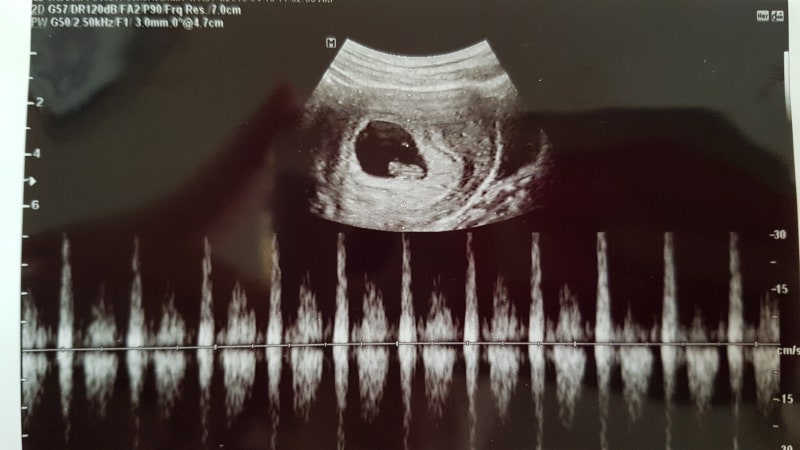

7주간의 진료로 아기의 심장 소리를 듣는 7주간의 진료까지는 질 초음파로 아기를 확인합니다!